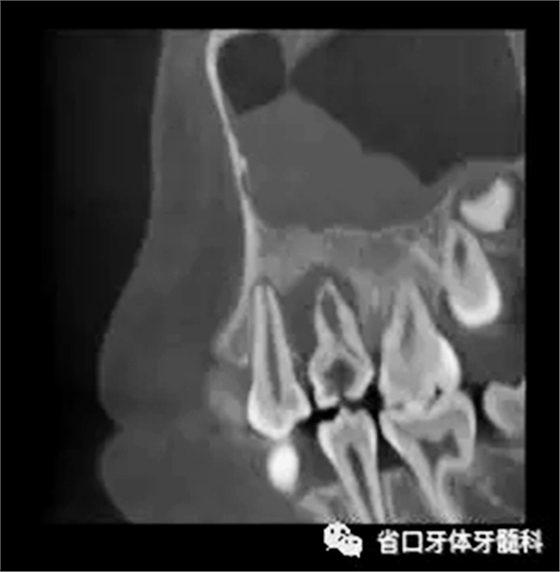

圖3 CBCT(2016-11-13):15由髓腔至根管內(nèi)見團(tuán)塊阻射影像,阻射影中央為透射影,根尖1/3處見根管膨大,腭側(cè)牙槽骨破壞,根尖周低密度影范圍大,上頜竇黏膜增厚。